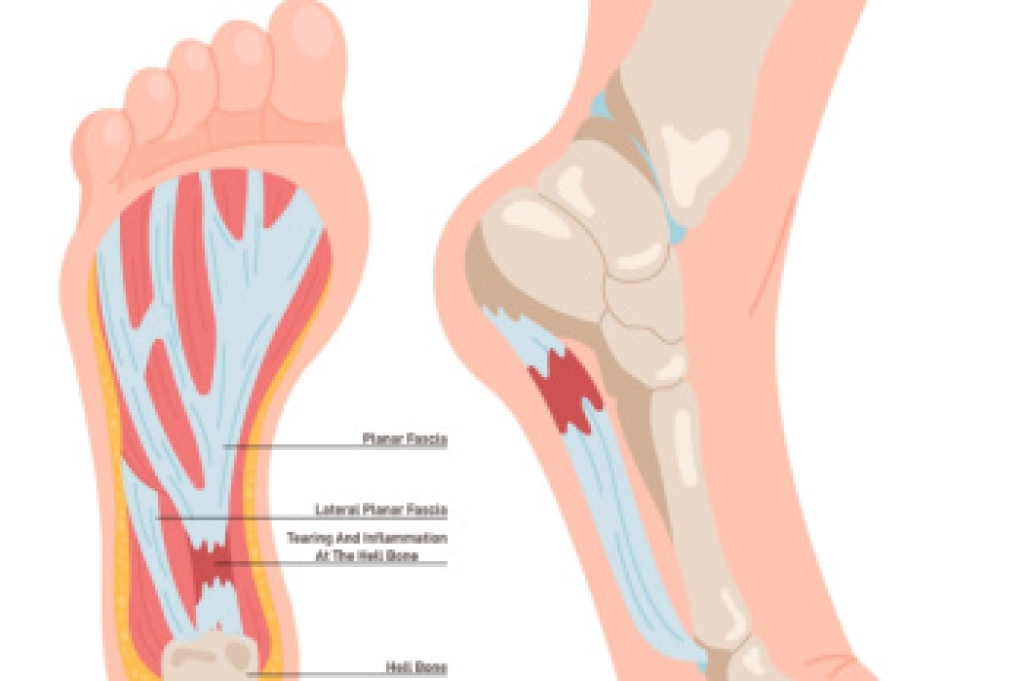

Plantar fasciitis is a foot condition characterized by inflammation and degeneration of the plantar fascia, a thick band of tissue that runs along the bottom of the foot, connecting the heel to the toes. This condition often develops gradually over time, resulting from repetitive strain and stress on the plantar fascia. Activities that involve prolonged standing, walking, or running, especially on hard surfaces, can worsen the problem. Additionally, factors such as obesity, tight calf muscles, high arches, flat feet, and non-supportive footwear can increase the risk of developing plantar fasciitis. Symptoms include heel pain, particularly in the morning or after periods of inactivity, which can worsen with activity. While plantar fasciitis can be challenging to manage, various treatment options, including rest, stretching exercises, orthotic devices, and in severe cases, corticosteroid injections or surgery, can help alleviate pain and promote healing. If you have persistent heel pain, it is strongly suggested that you consult a podiatrist who can accurately diagnose and treat the cause.

Plantar fasciitis is one of the most common causes of heel pain. The plantar fascia is a ligament that connects your heel to the front of your foot. When this ligament becomes inflamed, plantar fasciitis is the result. If you have plantar fasciitis you will have a stabbing pain that usually occurs with your first steps in the morning. As the day progresses and you walk around more, this pain will start to disappear, but it will return after long periods of standing or sitting.